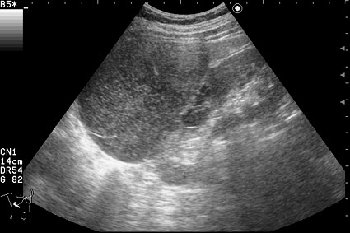

Сонограмма правой почки.

Нет, это кистоподобное образование, связанное с почкой.

Необычнвя картинка. В голову приходят самые "сумашедшие" предположения (в т.ч. малигнизация кисты, но нет кровотока, нагноившаяся киста, но нет реакции ее стенки; киста с густым содержимым, но отчего оно так загустело?). Просветите нас, пожалуйста.

Почечно-клеточный рак правой почки, кистозная форма.

Но только по густому содержимому кистозного компонента. Стенка тонкая, кровоток не прокрашивается (единичный мелкий срез сосуда в центре образования больше похож на артефакт, а м.б. им и является).

Если бы в этом случае и содержимое было бы более "жидким", вероятность постановки правильного диагноза была бы минимальной.

Я в своем заключении предположил кисту с внутренним кровоизлиянием.

И ошибся.